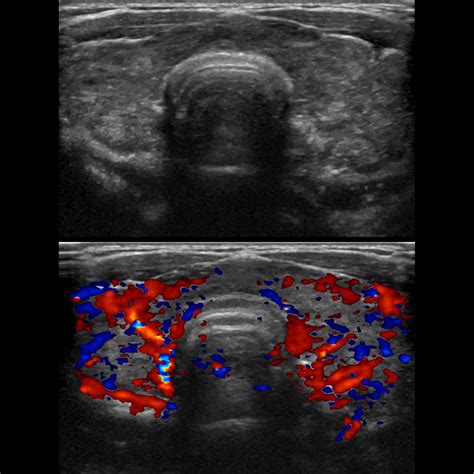

• Imaging Studies: Ultrasound, CT scans, or MRI may be used to visualize the thyroid gland and detect any abnormalities such as nodules or goiters.